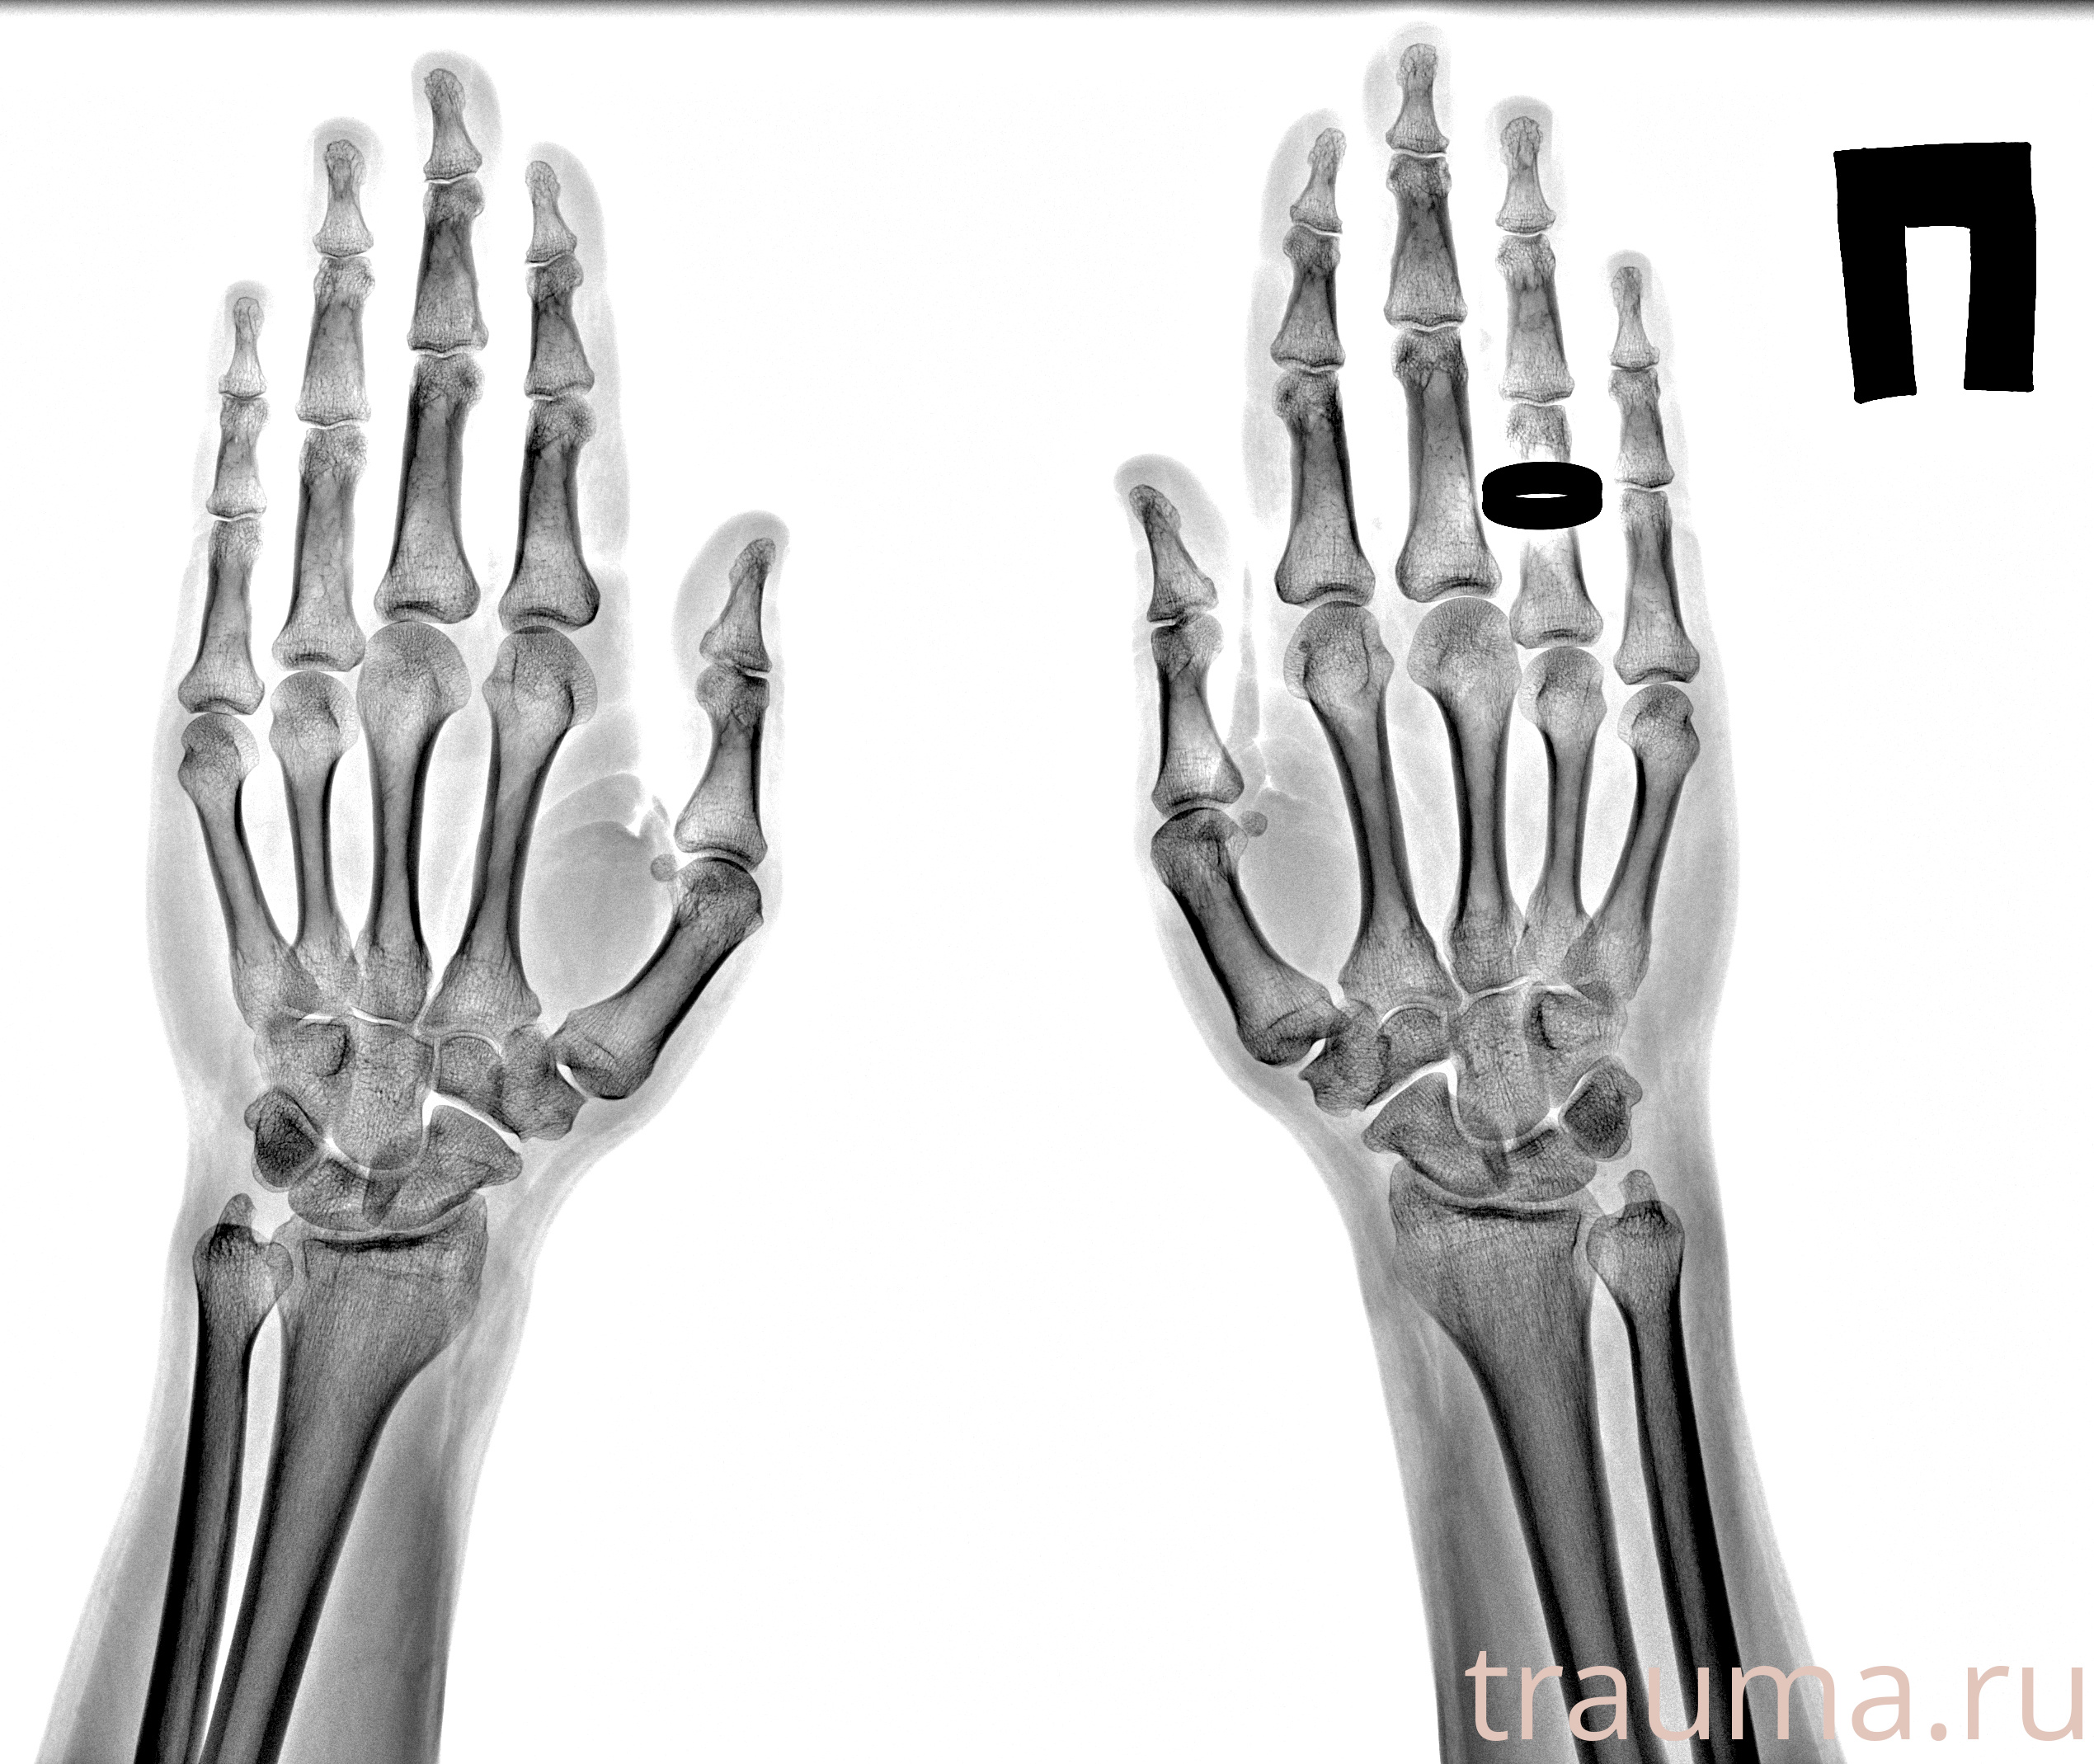

Рентгенограммы

Рентген на дому: по вашему адресу приезжает врач-рентгенолог, травматолог-ортопед с мобильным рентгеновским аппаратом, проводит диагностику травмы или заболевания, делает необходимые рентгенограммы, дает рекомендации по дальнейшему лечению. Получить качественные снимки в домашних условиях возможно благодаря уникальной методике, разработанной МосРентген Центром для института  Склифосовского